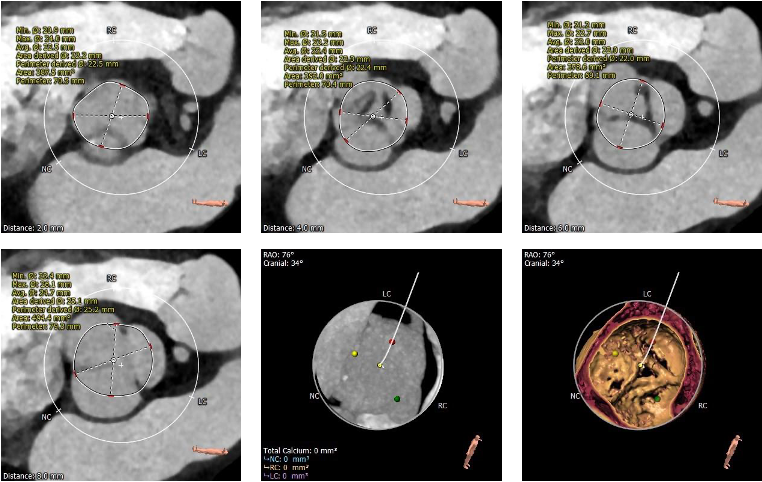

CT结果显示,患者为三叶式主动脉瓣,轻度钙化,瓣叶明显增生肥厚但未见明显融合,结合瓣上结构和左室流出道结构特点,较大可能影响瓣膜植入后的形态及贴壁性,存在瓣膜向下位移的风险,且大概率需要使用瓣中瓣策略完成手术。在瓣膜尺寸的选择上要更为精准,在瓣膜释放时,释放位置更要把握好。该患者还存在弓部夹角锐利,弓部宽度较短,且降主动脉扭曲,极大地考验了器械输送系统的过弓性能。

三叶式主动脉瓣, 瓣叶明显增厚,未见明显融合粘连,瓣叶钙化较低,假体瓣膜锚定难度较高,存在瓣膜位移风险,瓣中瓣风险偏高。

主动脉根部评估

冠脉阻挡风险评估

瓣环上解剖结构评估